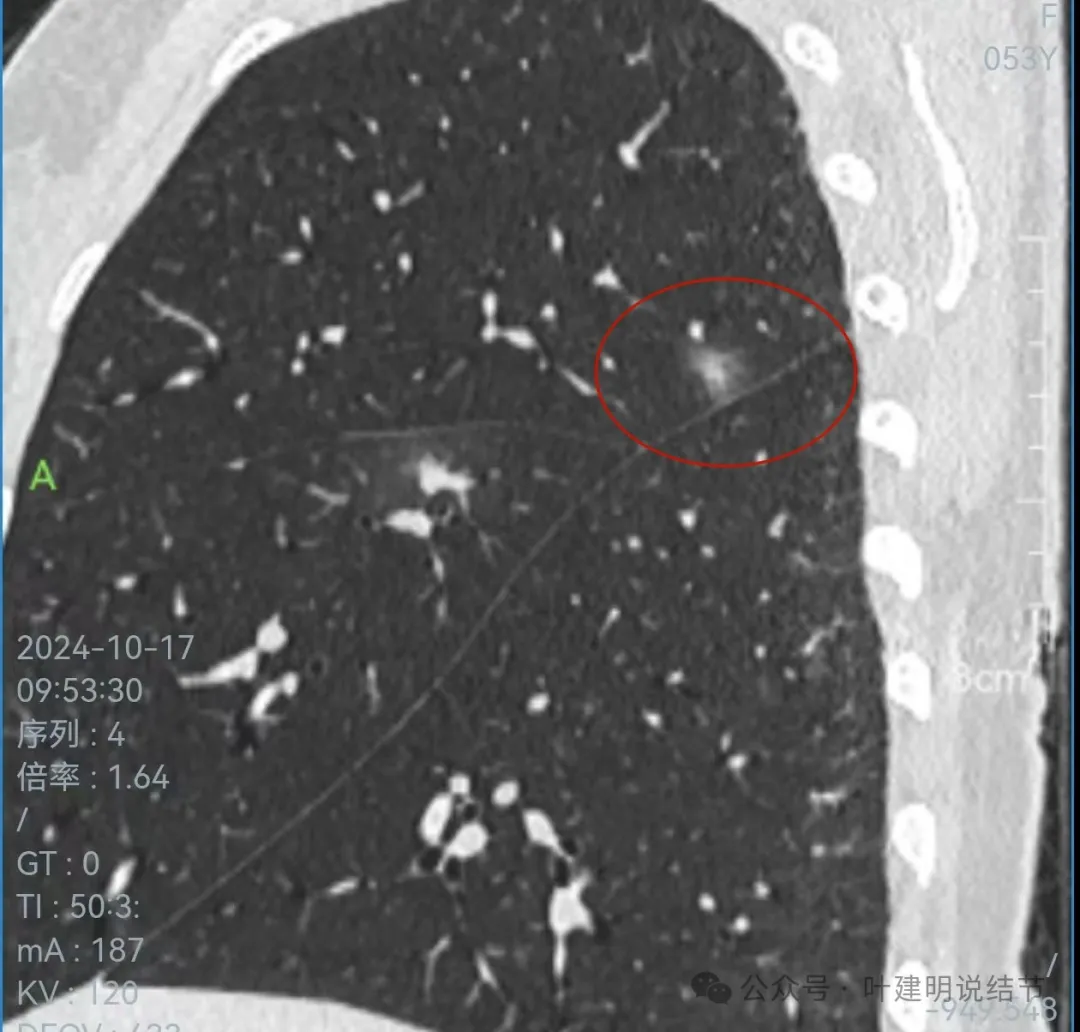

矢状位上看,病灶虽整体轮廓较清,但瘤肺边界显模糊,整体不致密。

冠状位上看病灶有实性成分,实性成分缺乏收缩力,外围是淡磨玻璃成分,瘤肺边界欠清,贴着叶裂没有影响。

从连续层面以及影像细节上看,这个病灶就不可能是恶性的!短期内出现,混合密度而瘤肺边界不清,整体缺乏收缩力也无膨胀性,灶内实性成分不致密且磨玻璃成分过淡,灶内血管有异常增粗与密度过高,又是两肺多发病灶。这所有的表现与病情发展都与感染性病变契合,周围淡磨就是炎症水肿的关系,血管异常就是管壁有炎症的关系,多发就是感染(致病因素)影响两肺的关系。怎么可能是恶性?